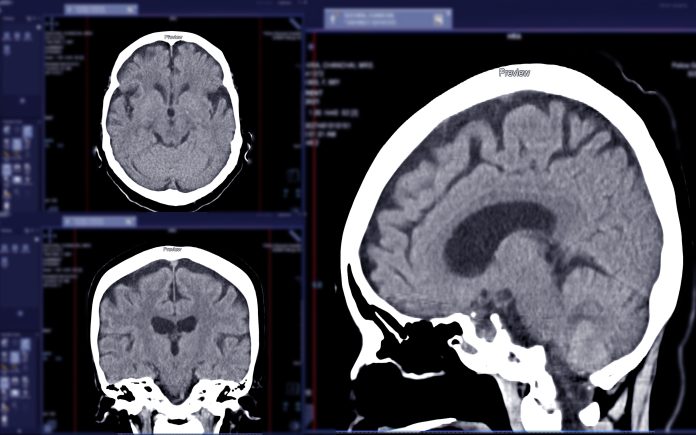

Researchers at King’s College London have developed an AI model that can detect strokes, brain tumours, and aneurysms from MRI scans, helping doctors make faster, more accurate diagnoses

Researchers at King’s College London have made a significant advance in medical imaging by developing an AI model that accurately detects strokes, brain tumours, and aneurysms in MRI scans. This groundbreaking technology aims to enhance the speed and accuracy of diagnoses, reduce radiologists’ workload, and ultimately improve patient outcomes by enabling faster identification of critical cases requiring immediate attention. The detailed findings of this study have been published in the reputable journal Radiology AI.

In a series of rigorous tests, the AI model was evaluated on its ability to identify specific neurological conditions, including strokes, multiple sclerosis, and brain tumours. This testing involved using MRI scans that were not included in the model’s training dataset. Remarkably, the AI successfully recognised these conditions with high precision, confirming its robustness in clinical settings.